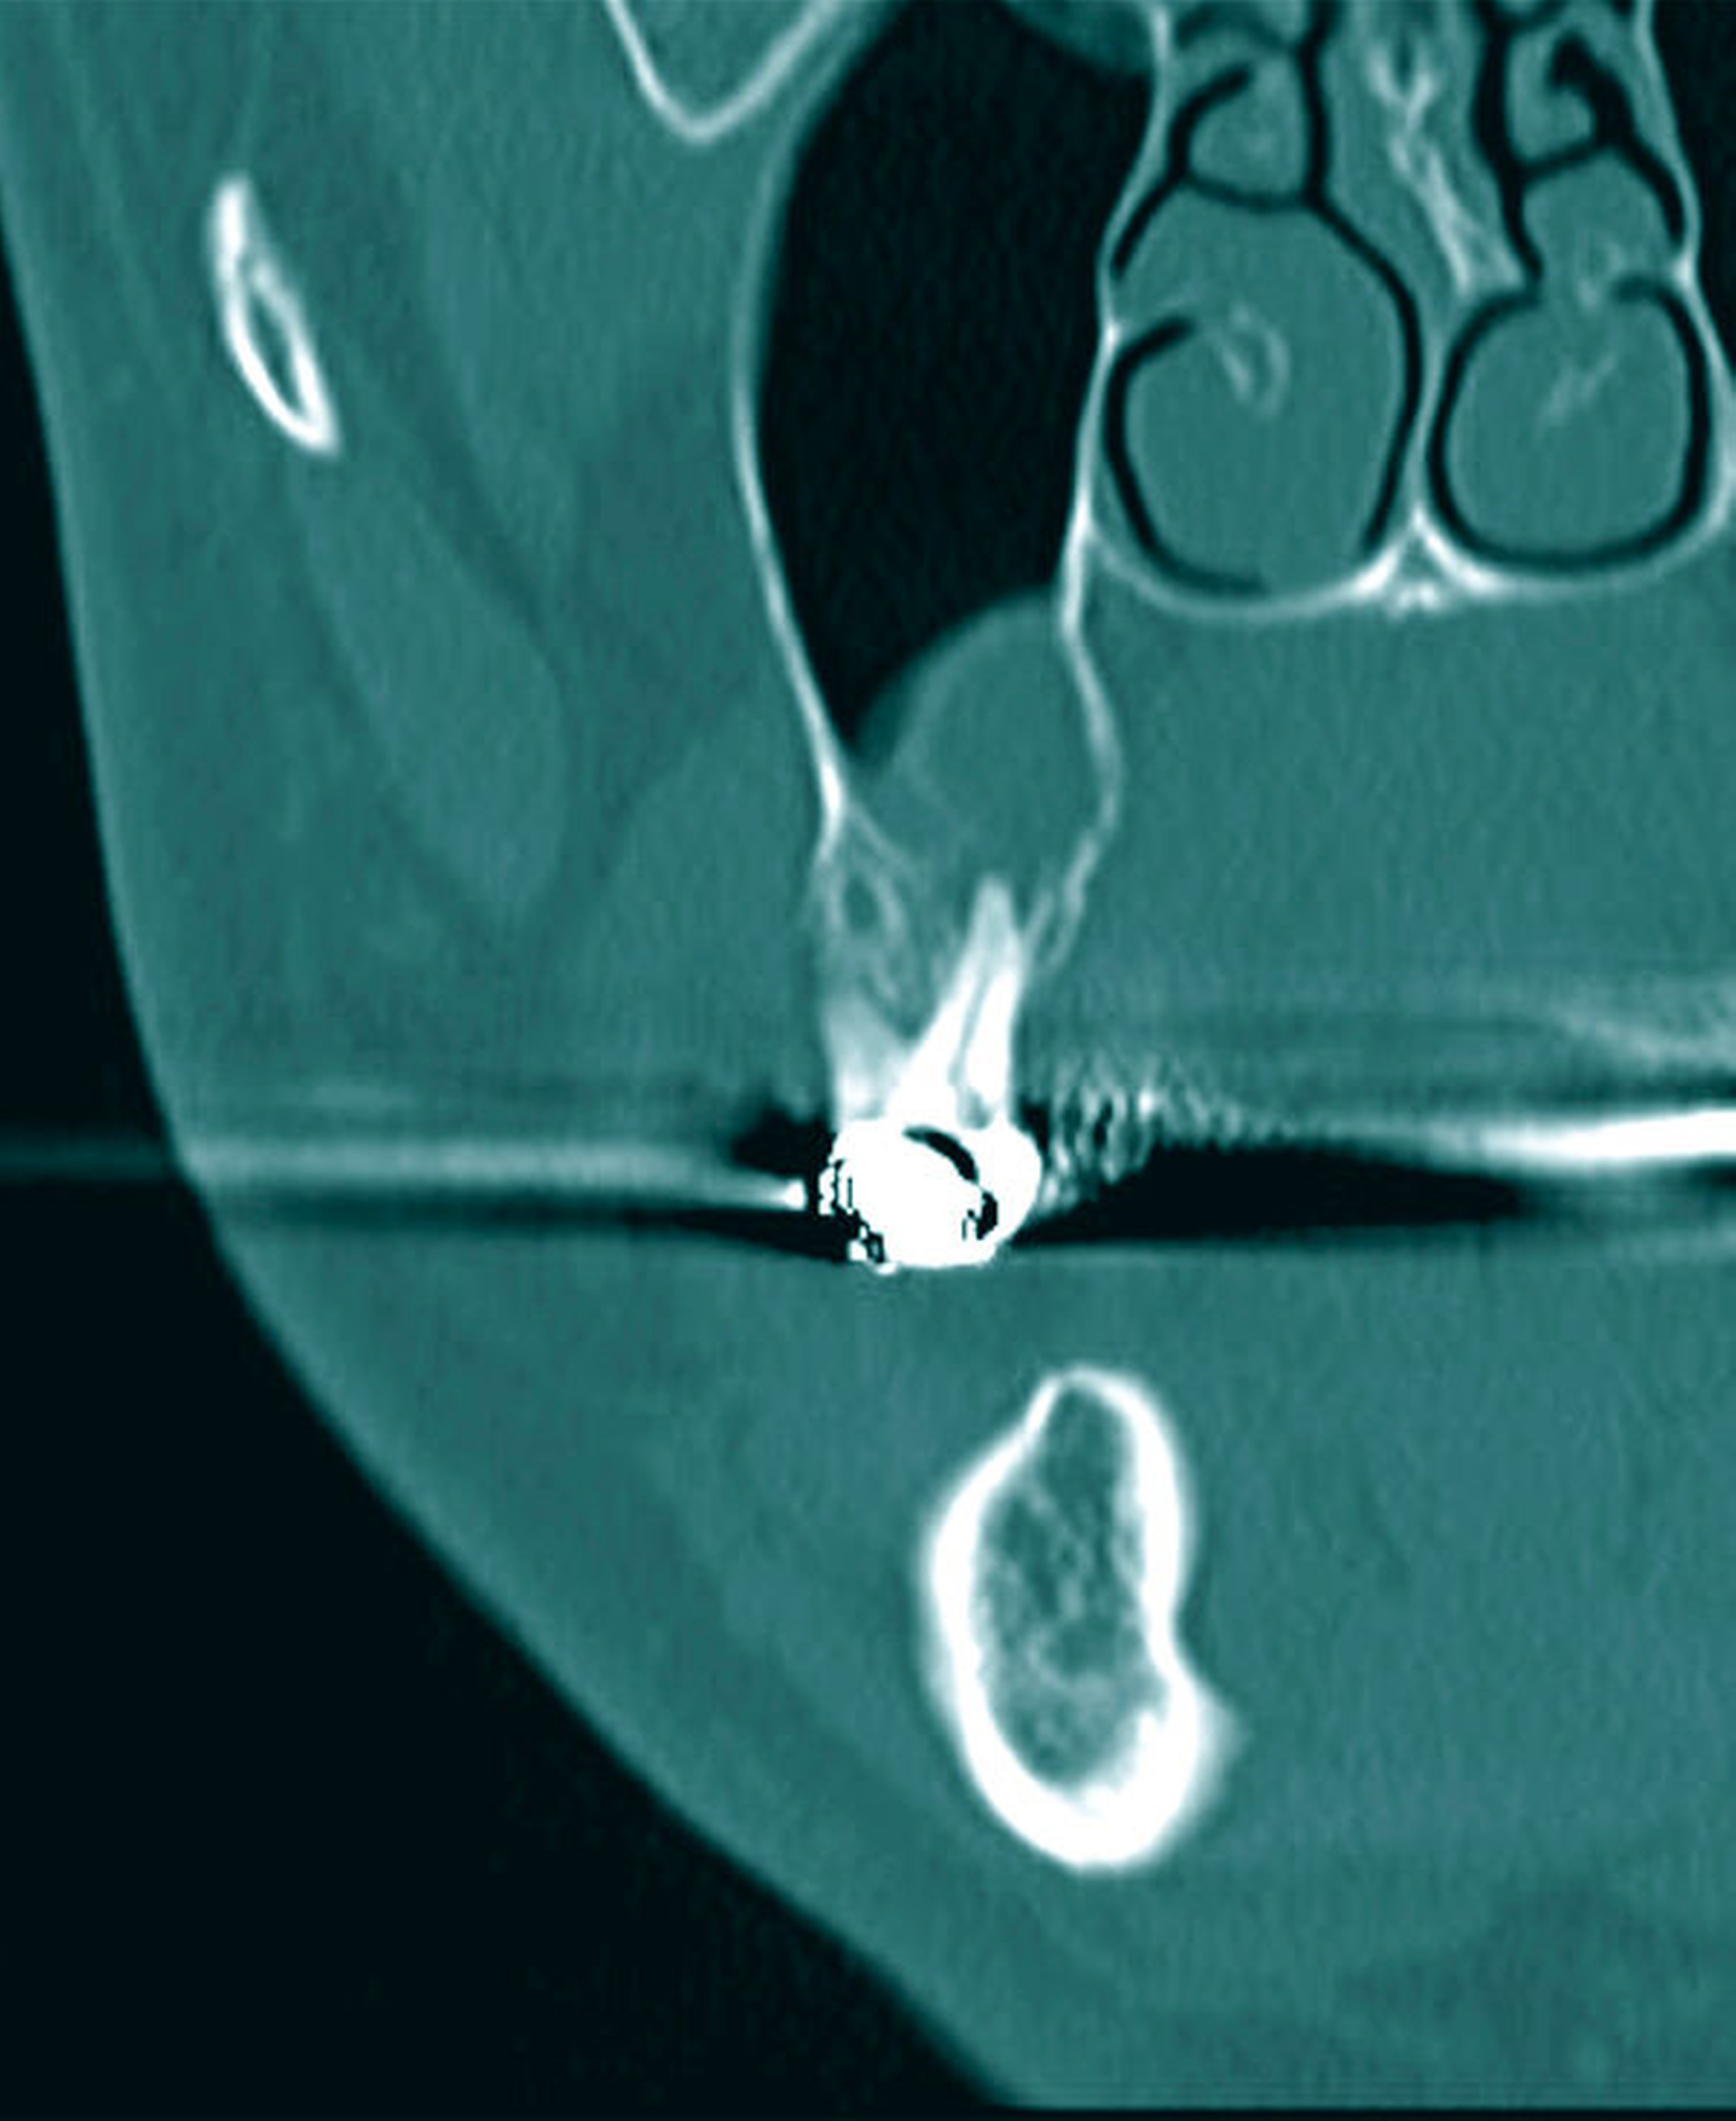

Das anschließend durchgeführte DVT wies an der besagten Stelle eine weichgewebsdichte, scharf begrenzte, ovale Struktur mit stellenhafter Unterbrechung der Kompakta auf, die bis in die Kieferhöhle ragte (Abbildungen 3 und 4).